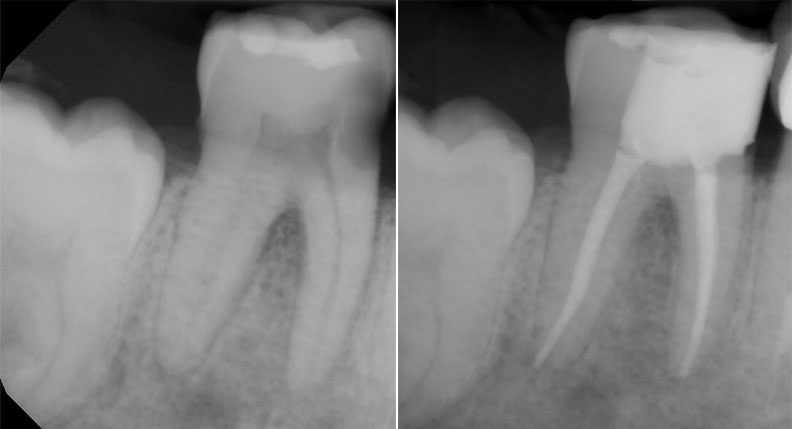

Endodontics

Endodontic treatment, commonly known as root canal therapy, is vital when the nerves of your teeth are damaged due to fractures, deep decay, or trauma. This procedure removes the infected or damaged nerve tissue, cleans the inside of the tooth, and seals it to prevent further infection. By preserving the natural tooth, endodontics allows you to maintain the function and aesthetics of your smile.